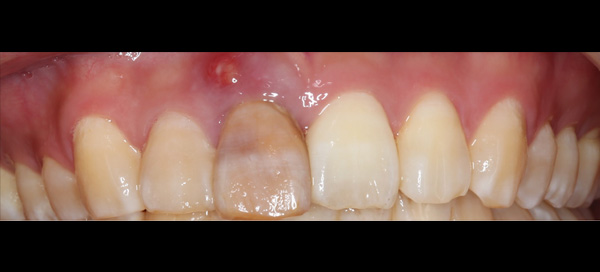

| 主訴 | 前歯が腫れた |

| 治療期間 | 約18ヶ月 |

| 費用 | 700,000円 |

| 治療内容 | インプラント、部分矯正、骨造成、結合組織移植、セラミック修復 |

| 治療に伴うリスク | インプラント周囲炎 セラミックの破折、脱離 |